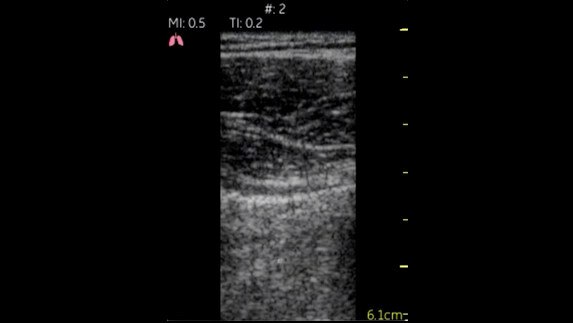

Lungs